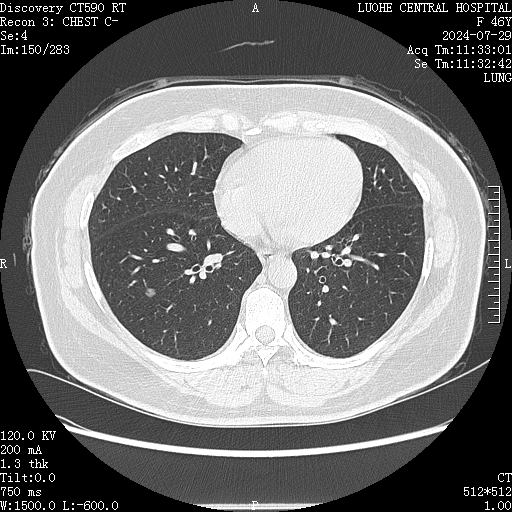

近日,漯河市中心医院心胸外科收治肺结节患者一名,48岁女性,CT检查发现右下肺结节(直径7mm),术前阅片考虑恶性可能,行胸腔镜下切除,术后病理提示微浸润性腺癌(早期肺癌)。近年来这样的病例越来越多,医院心胸外科每年收治类似病例近300余例。

胸部影像学表现为直径≤3cm的局灶性、类圆形、密度增高的实性或亚实性肺部阴影,可为孤立性或多发性,不伴肺不张、肺门肿大和胸腔积液。病灶直径≤3cm的称为肺结节,病灶直径>3cm的称为肺肿块。

影像学检查:胸部低剂量CT扫描或高分辨CT扫描是发现肺结节的主要手段。PET-CT:部分需要鉴别是否为恶性肿瘤或者多发肺结节需要除外转移性肺癌时需要,不建议所有肺结节病人都做PET-CT。生物标志物检测:肿瘤标志物,某些血液检测可以帮助判断结节的性质。气管镜检查:能够发现位于气管、支气管内或旁边的肺结节。活检:对于疑似恶性的结节,还需要进行活检穿刺或者胸腔镜活检以确定其性质。